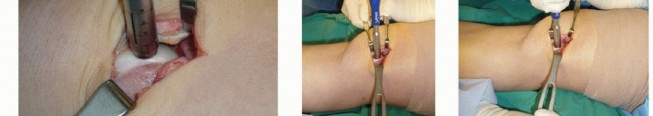

Large OLTs are usually identified on plain radiographs (

FIG 1

).

FIG 1 • Radiographs. A. AP radiograph of the ankle suggests symmetric alignment and a medial talar dome defect. B. Mortise view also suggests medial OLT. C. Lateral view shows anatomic alignment, with OLT less obvious.

We routinely obtain simulated weight-bearing radiographs at 6 weeks and 10 weeks, and again at 14 to 16 weeks, depending on the progression of healing. If there was a concern about fixation of the graft or osteotomy, then radiographs are also obtained at the first postoperative visit (

FIG 4

FIG 4 • Postoperative radiographs. A,B. AP and mortise views showing anatomic reduction of medial malleolar osteotomy. C. Sagittal view.